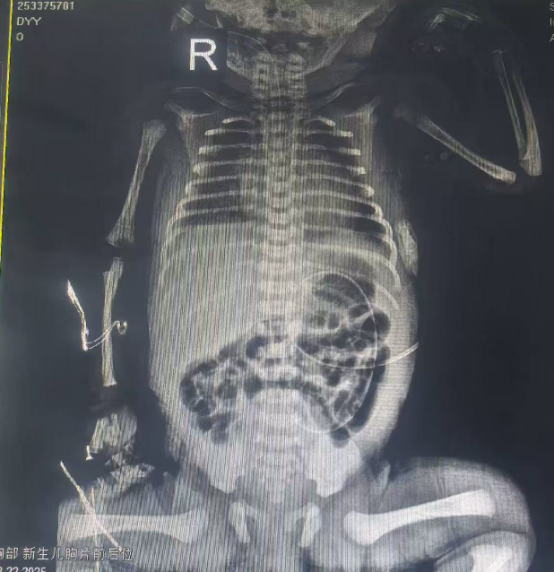

入院后,小雪儿病情迅速恶化。即便在无创呼吸机辅助通气下,末梢血氧饱和度仅维持在70%-80%,肤色苍白如纸。结合临床表现,救治团队高度怀疑胎母输血可能,且已出现失血性休克迹象。医护人员迅速行动——建立静脉通路、完善血常规、胸部正位片、溶血实验、输血前四项及甲胎蛋白等相关检查,一场与时间赛跑的生命救援全面展开。

在新生儿科副主任医师张东平的带领下,主治医师贾毅、主管护师武佩佩、护士居姣姣及唐荣等护理骨干迅速组成救治小组,全力投入救治。检查结果令人揪心:新生儿正常血红蛋白值为170-220g/L,而小雪儿的血红蛋白仅为正常值的五分之一,极重度贫血合并心力衰竭,脑钠肽高达89136pg/ml!